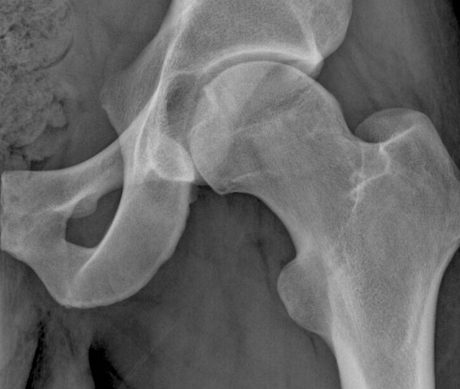

• Crossover sign - anterior wall extends lateral to the posterior wall

• Ischial spine sign - ischial spine projects more medially than normal into the pelvis

Normal hip - anterior acetabular wall (red line) is medial to the posterior acetabular wall (green line). Also note the ischial spine (blue line) isn’t overly projected into the pelvis